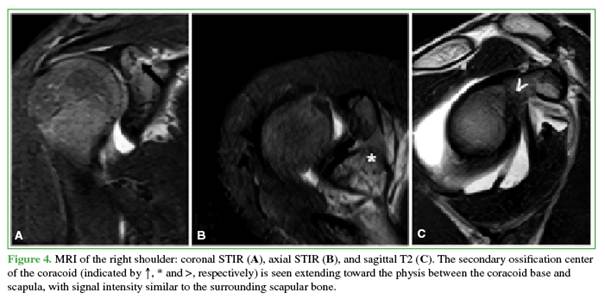

In this case, comparison radiographs of the contralateral shoulder (Figure 3) and MRI (Figure 4) were obtained to confirm the diagnosis and identify associated injuries. Given favorable clinical progress within the first 48 hours and the absence on MRI of findings suggestive of fracture or injury to the epiphyseal growth plate at the base of the coracoid, conservative treatment was indicated: analgesics for 3 days followed by a progressive return to sports over 21 days. The patient progressed well and returned to sports without restrictions.

The scapular secondary ossification centers include two main components (Figure 5): 1) Coracoid secondary ossification center: the first scapular secondary center to appear; it contributes to the upper third of the glenoid articular surface. It typically appears between 9 and 12 years and fuses with the scapular body between 12 and 16 years; 2) Inferior glenoid secondary ossification centers: multiple centers arranged in a horseshoe configuration that form the lower two-thirds of the glenoid. These usually appear between 11 and 14 years and fuse between 12 and 16 years.5 Comparison radiographs of the contralateral shoulder are an important tool, allowing reliable distinction between a pathologic fracture line and a normal physis.6,7 On CT, ossification centers appear on all planes as linear foci of bone and should not be confused with fracture lines, as occurred here. Similar diagnostic confusion has been reported—e.g., Galán-Olleros et al.8 described a comparable case in a 13-year-old basketball player—highlighting how common and relevant this pitfall is in pediatrics.